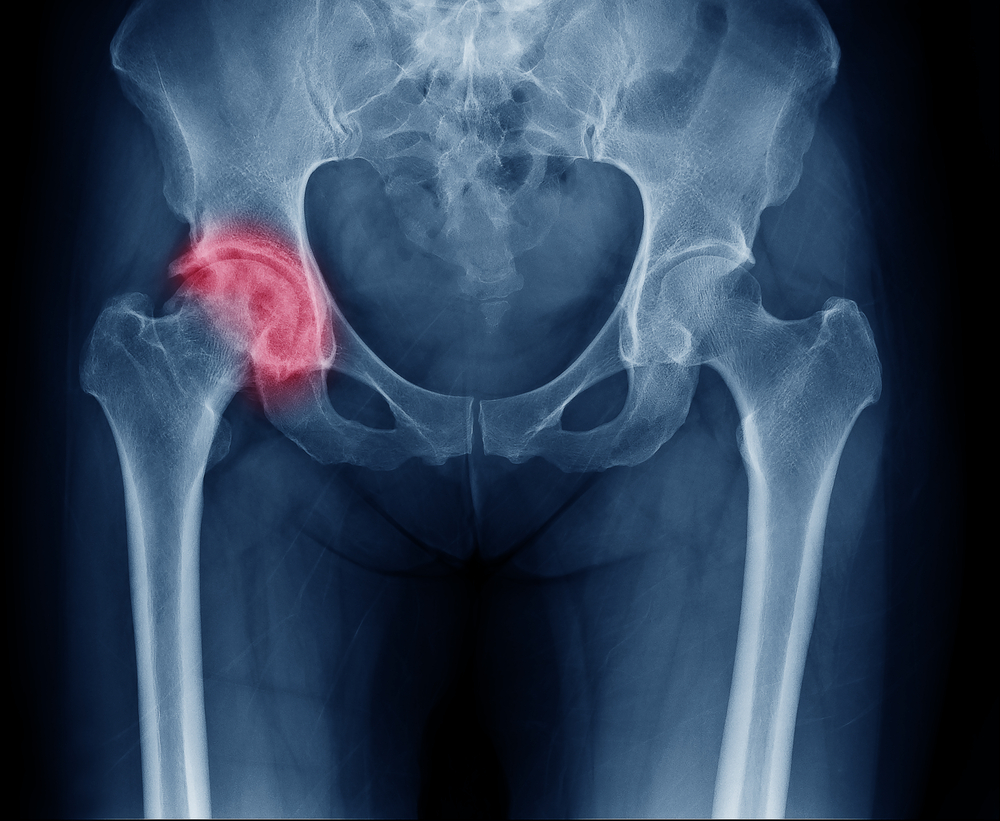

L’articolazione dell’anca, o articolazione coxo-femorale, è formata da due capi ossei sferici, uno concavo definito acetabolo e l’altro convesso ossia la testa del femore che ruota liberamente all’interno dell’incavatura acetabolare.

La displasia dell'anca è un’anomalia dell’articolazione dell’anca in cui la testa del femore si sposta dalla cavità acetabolare.

Nell'adulto è utile, invece, la radiografia dell'anca per individuare l’anomalia.